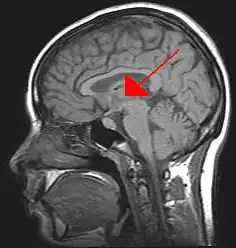

De thalamus,[7] afgeleid van het Griekse θάλαμος, thálamos, slaapkamer,[8] is een belangrijke hersenkern. Samen met de hypothalamus en de daaraan hangende hypofyse wordt het tot het diëncephalon, tot de tussenhersenen gerekend. Het is een, evolutionair gezien, zeer oude hersenkern.

De thalamus legt in de hersenen de verbindingen. Dat zijn de verbindingen tussen de grote hersenen en de kleine hersenen én tussen de hypothalamus en de grote hersenen. Hier worden de signalen tussen het perifere zenuwstelsel en de hogere lagen van de hersenen gecoördineerd. De thalamus is een belangrijk verbinding voor allerlei informatie van zintuigen op weg naar de hersenschors, maar vormt ook een onderdeel van circuits in de hersenen die betrokken zijn bij de sturing van beweging en emoties. Een belangrijke kern in de thalamus is het corpus geniculatum laterale, dat een belangrijke rol speelt bij het overbrengen van het beeld van de ogen naar de hersenen.

Er zijn eigenlijk twee thalami, in elke grote hersenhelft een. Bij 70% van de mensen zijn ze met elkaar verbonden. Deze verbinding wordt de adhaesio interthalamica of ook wel massa intermedia genoemd. De thalamus is opgebouwd uit veel verschillende kernen van zenuwcellen. De voornaamste twee kerngroepen[9] zijn: